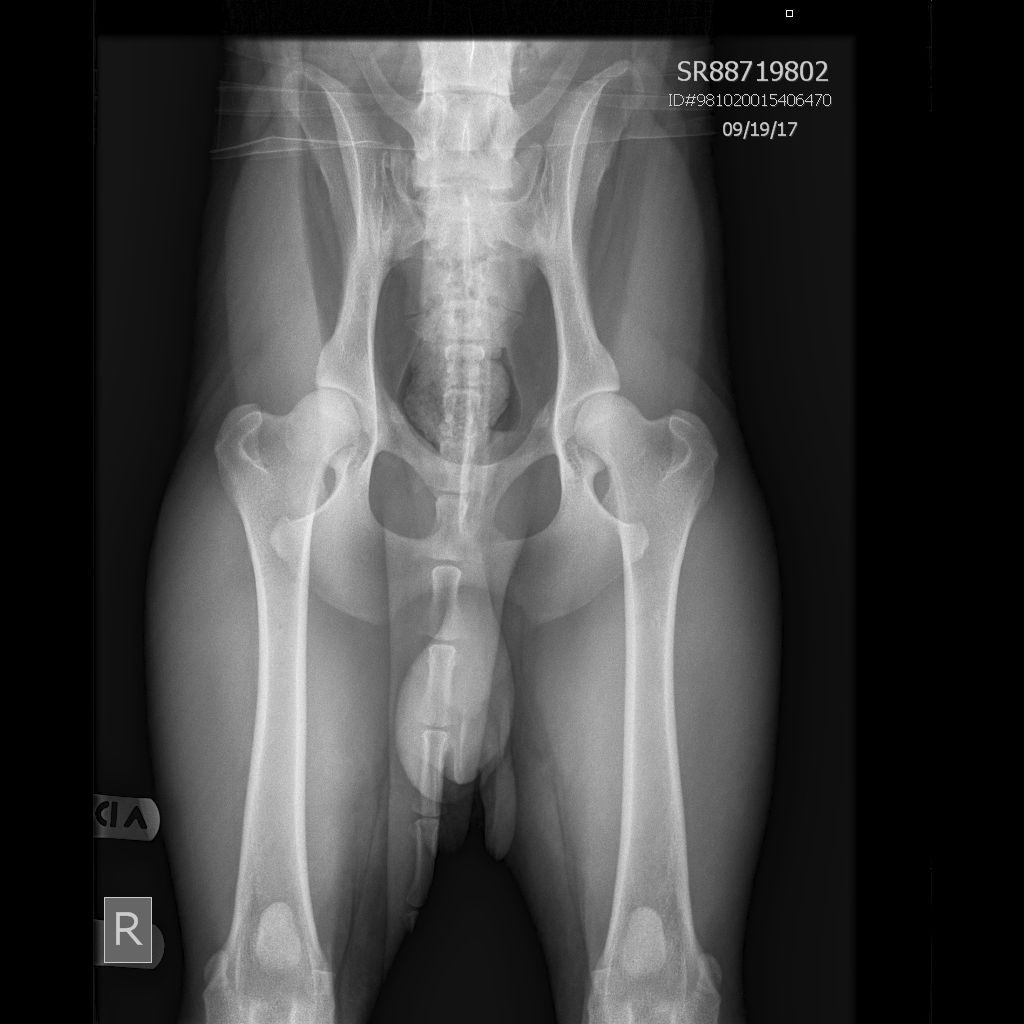

OFA Hips Good IR-12232G227M-VPI